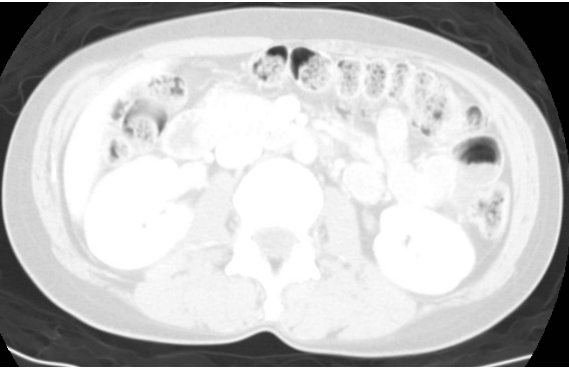

36.下圖中CT影像所呈現為下列那一項window的設定?

(A)abdomen (B)mediastinum (C)bone (D)lung